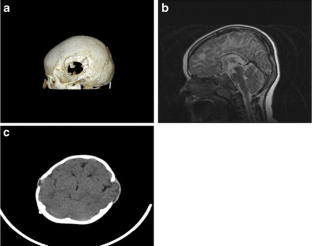

Fig. 3